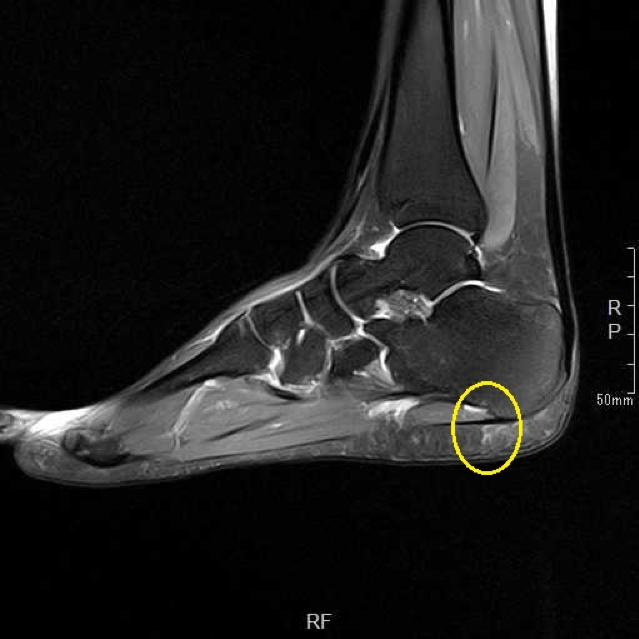

保存的治療で十分な改善が見られなかったため、より詳しく状態を調べるためにMRI検査を実施しました。その結果、足底腱膜の付着部(踵の骨にくっついている部分)と、その周囲の脂肪組織に変性(組織の質が変わってしまうこと)が認められました。

1ヶ月間の保存的治療で日常歩行は可能になりましたが、素足での痛みが残存していました。MRI検査で足底腱膜の付着部と脂肪組織の変性を認めたため、このような慢性的な変性に対しては体外衝撃波治療が効果を示す可能性があるという報告に基づき、治療をご提案しました。